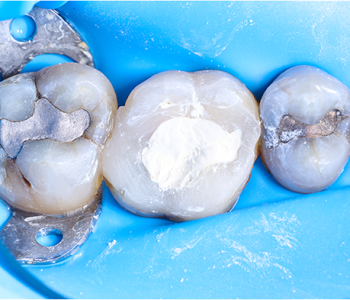

Este caso clínico demuestra los conceptos básicos de la técnica BioBulk Fill para la protección pulpar indirecta, utilizando el material Biodentine™ XP como sustituto de…

Sumérgete en esta conferencia exclusiva de la Dra. Mercadé para aprender nuevas estrategias para gestionar eficazmente las cavidades profundas utilizando Biodentine™ con la técnica BioBulk…

Descubre cómo el Dr. Renner aprovecha las propiedades mecánicas únicas de Biodentine™ para usarlo como material de núcleo permanente en la colocación de una corona…